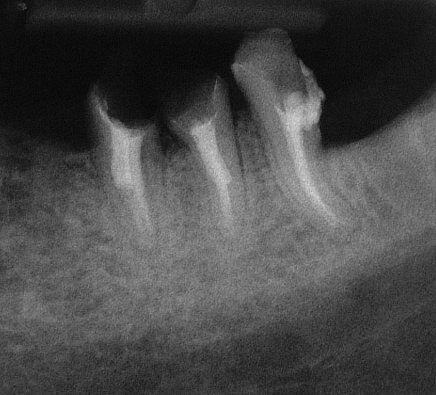

Neupatient, 3. Quadrant im November 2002 (Klick!)

Das OPT war insbesondere im distalen Bereich des 38 nicht ausgesprochen scharf. Wenn man sehr genau hinschaut, kann man die sich anbahnenden Schwierigkeiten jedoch erkennen. Auch der 37 wirkt nicht besonders aufregend.